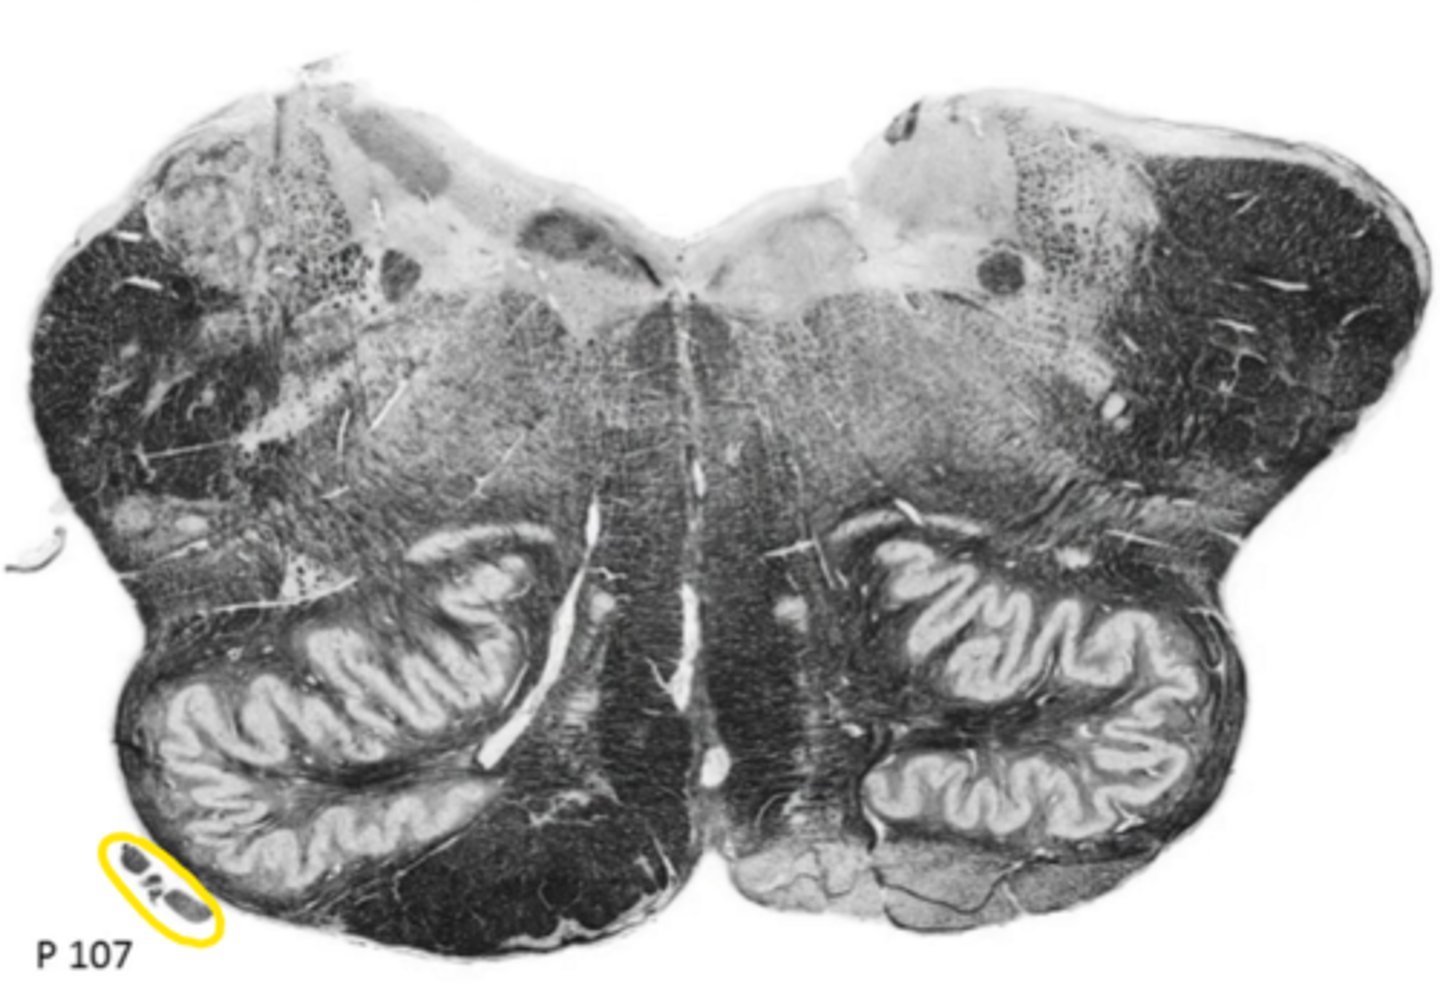

closed medulla

ID the brainstem level